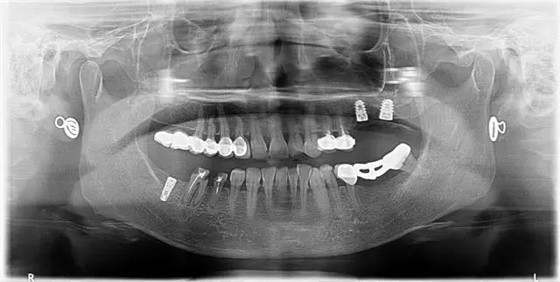

4、 全景片

1、治療前

2、治療后